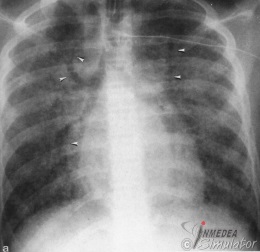

Abbildung: Innerhalb Verdichtung im rechten Lungenmittellappen, verursacht durch ein pneumonisches Infiltrat, sind luftgefüllte Bronchien erkennbar.

Konfluierende, unscharf begrenzte, kleinfleckige oder rosettenförmige Verdichtungen, Bronchopneumogramm.

Abbildung: Beispiel Mittellappenpneumonie. In Umgebung des Bronchopneumogramms multiple konfluierende fleckförmige Verschattungen.

Abbildung: Beispiel alveoläres Lungenödem. Über beide Lungen diffus verteilte, unscharf begrenzte Herde mit Tendenz zur Konfluation und Ausbildung eines Bronchopneumogramms.